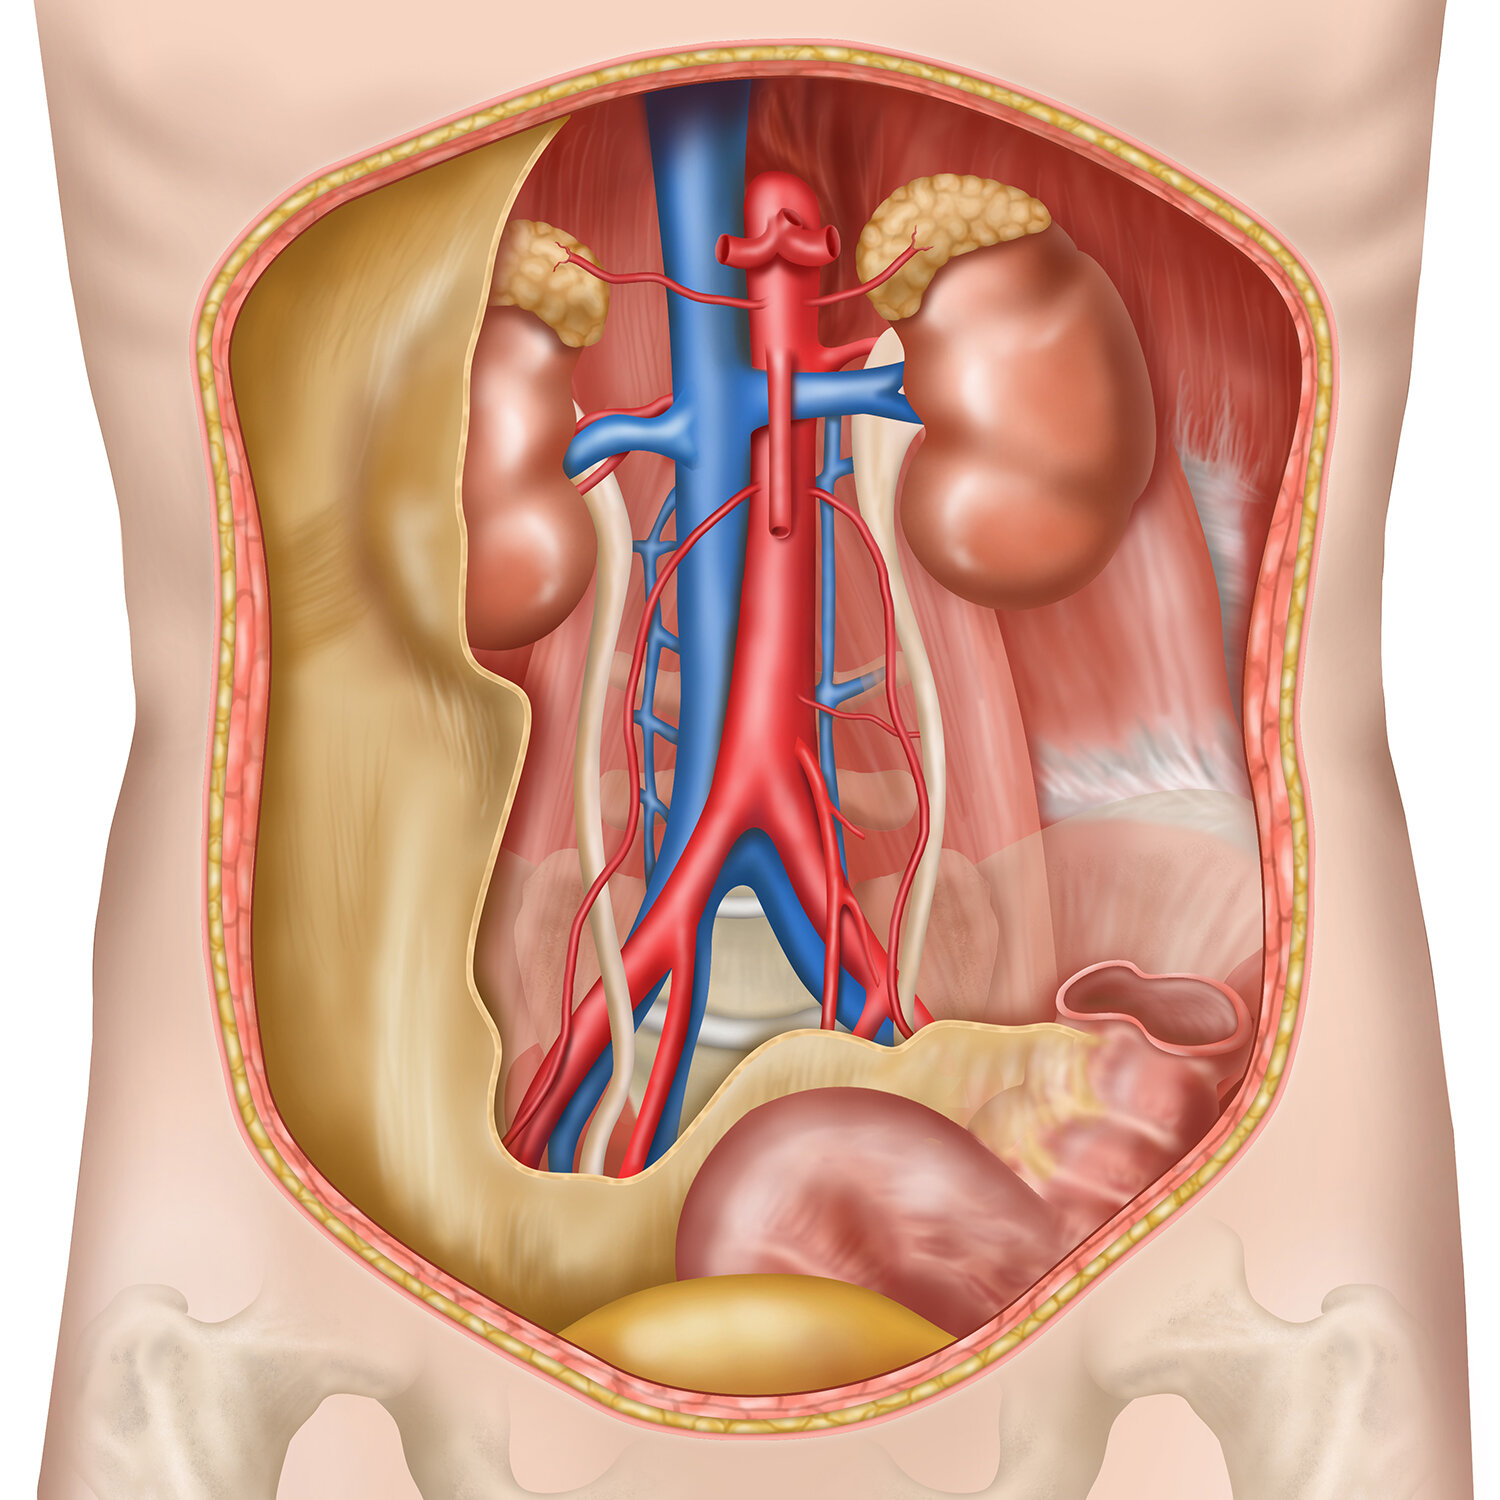

![Retroperitoneal space]()

Retroperitoneal space